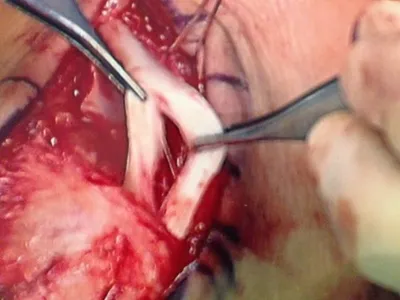

This is a pic of us relocating the tendons.

The following pic is of us debriding the side of the fibula to allow the ligament and tissue to connect to the fibula during healing so the tendons do not dislocate.

This is a pic of the suture passing through the fibula to attach the retinaculum and tissue so the peroneal tendons do not dislocate or sublux.